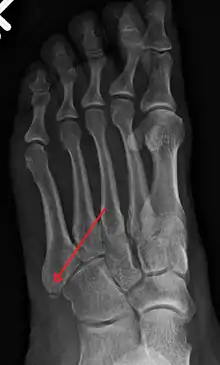

X-ray of foot.

The metatarsal bones are often broken by association football players. These and other recent cases have been attributed to the lightweight design of modern football boots, which provide less protection to the foot. In 2010 some soccer players began testing a new sock that incorporated a rubber silicone pad over the foot to provide protection to the top of the foot.[7] Stress fractures are thought to account for 16% of injuries related to sports participation, and the metatarsals are the bones most often involved. These fractures are sometimes called march fractures, based on their traditional association with military recruits after long marches. The second and third metatarsals are fixed while walking, thus these metatarsals are common sites of injury. The fifth metatarsal may be fractured if the foot is oversupinated during locomotion.[8]